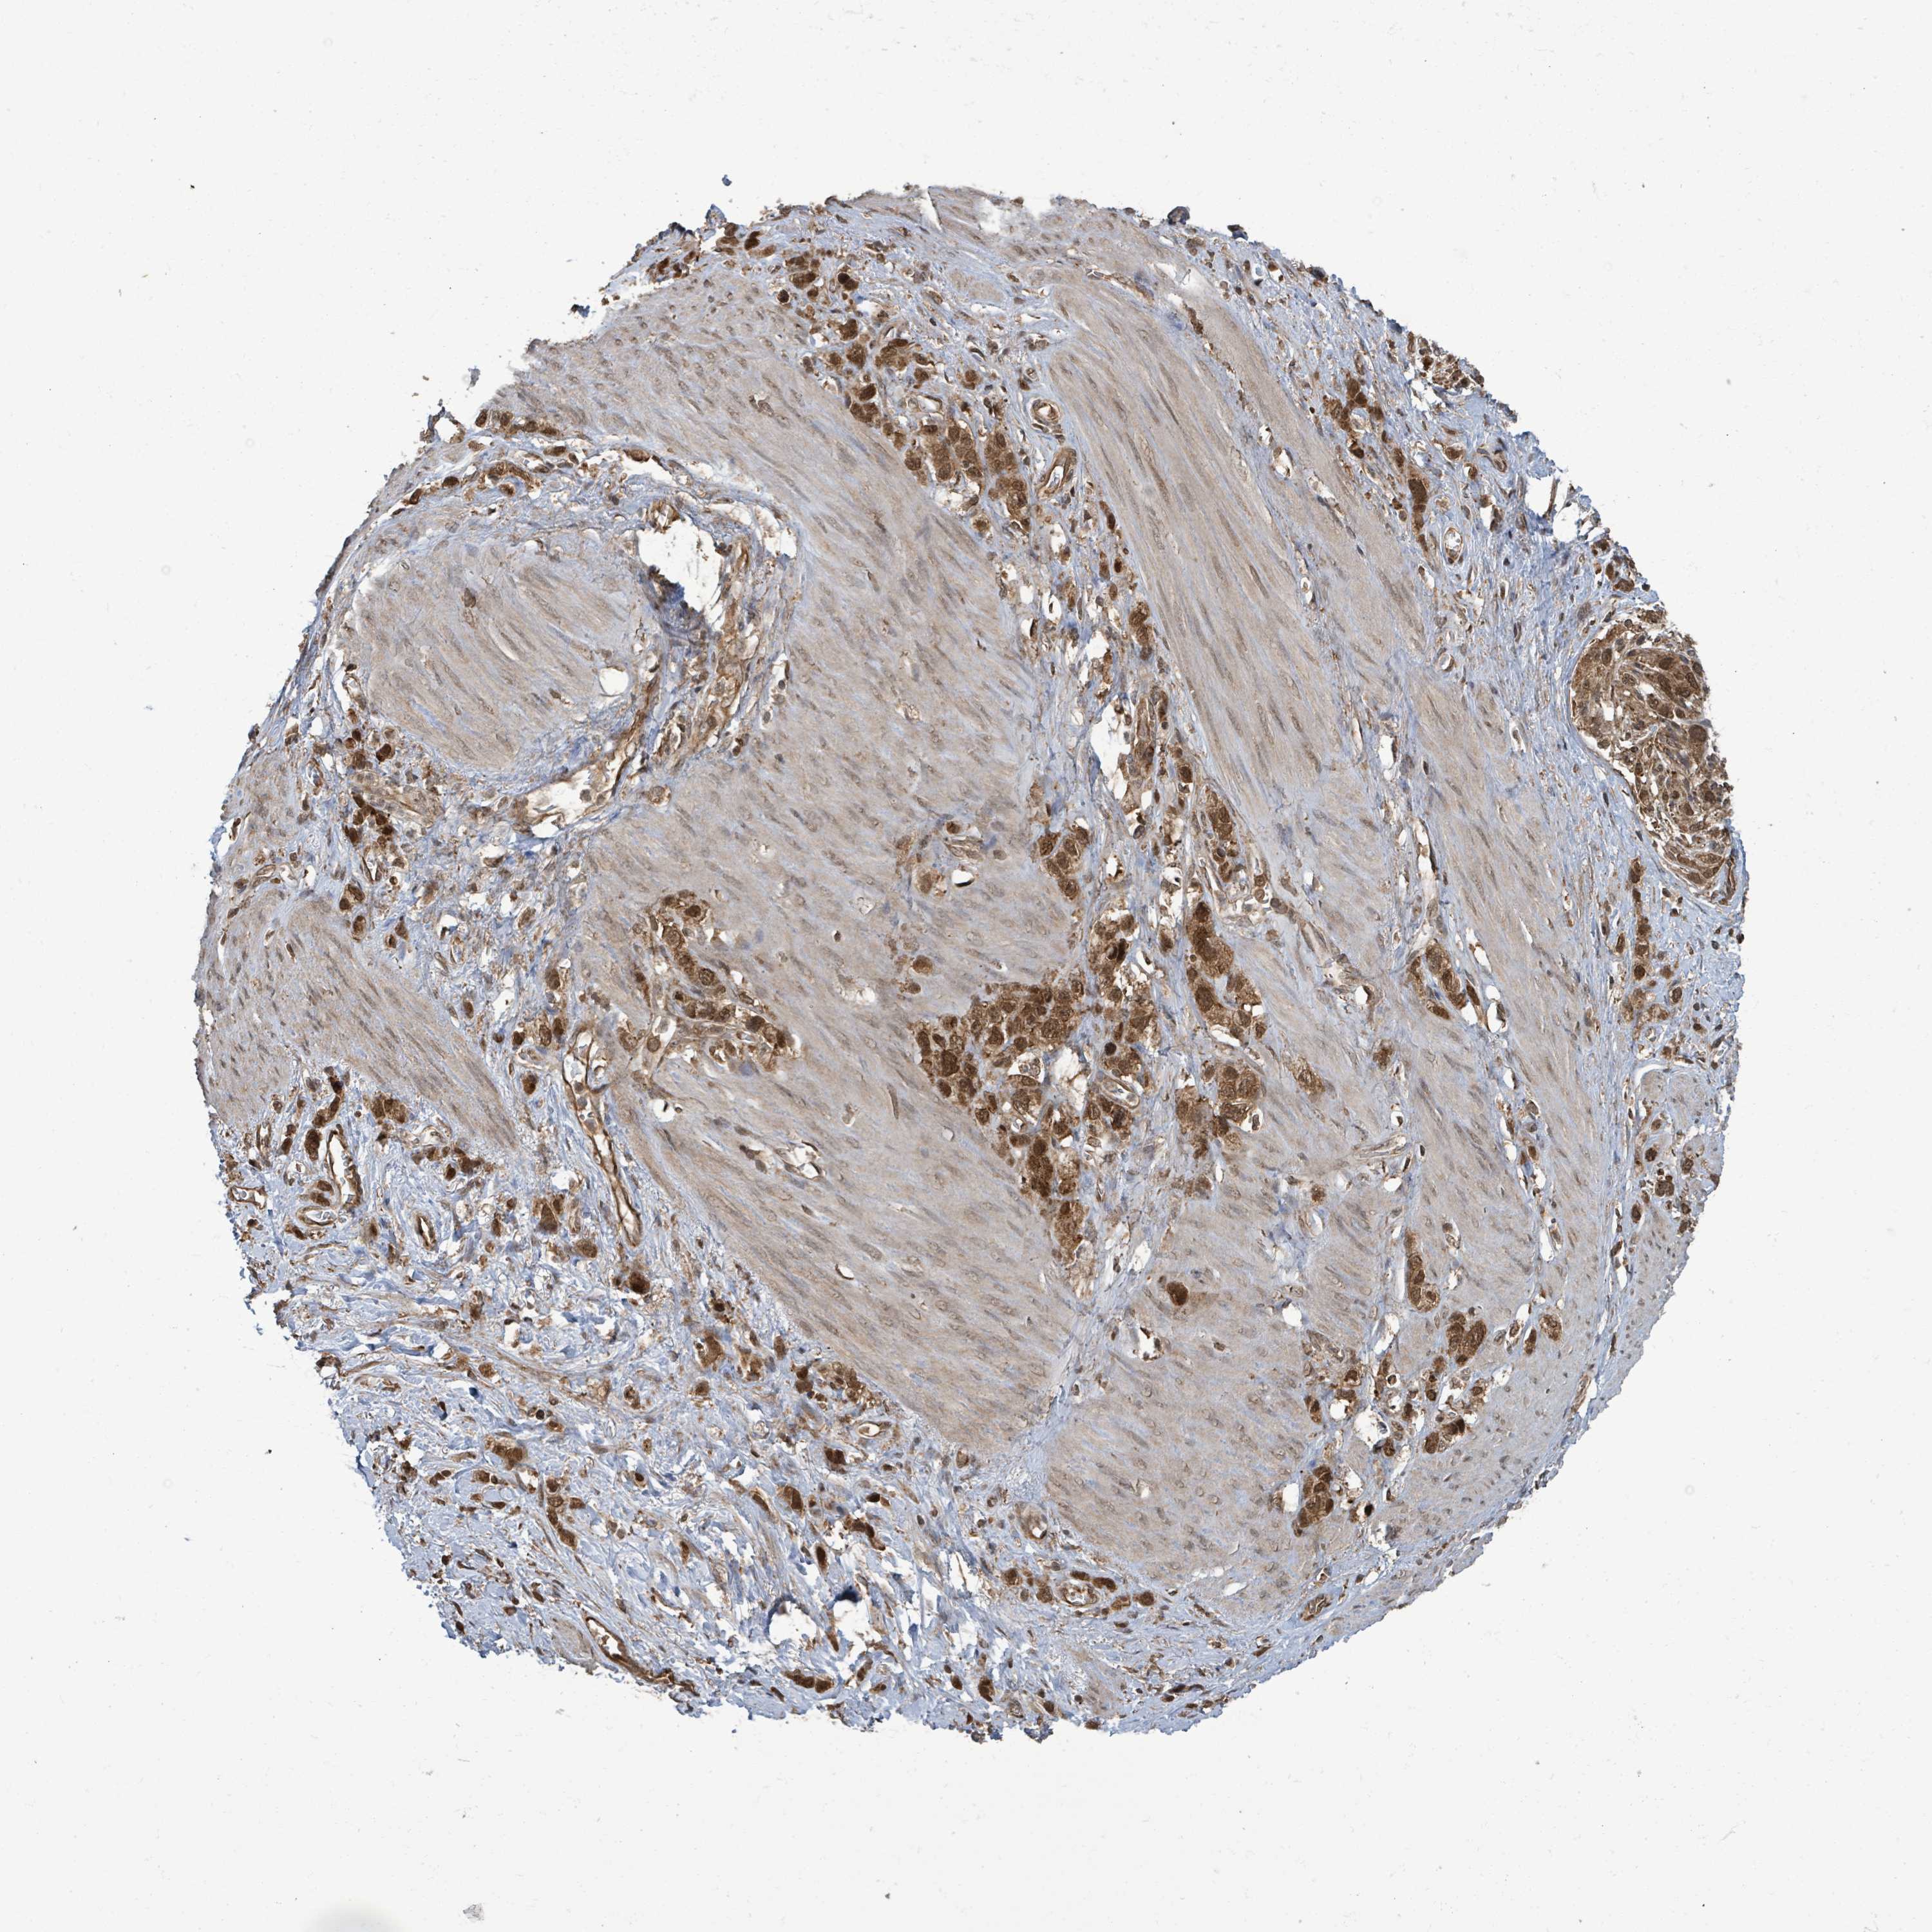

STOMACH CANCER - Protein expressioni

A mouse-over function shows sample information and annotation data. Click on an image to view it in a full screen mode. Samples can be filtered based on level of antibody staining by selecting one or several of the following categories: high, medium, low and not detected. The assay and annotation is described here.

Note that samples used for immunohistochemistry by the Human Protein Atlas do not correspond to samples in the TCGA dataset.

Antibody stainingi

Antibody staining in the annotated cell types in the current human tissue is reported as not detected, low, medium, or high, based on conventional immunohistochemistry profiling in selected tissues. This score is based on the combination of the staining intensity and fraction of stained cells.

Each image is clickable and will lead to virtual microscopy that enables deeper exploration of all samples and also displays staining intensity scores, fraction scores and subcellular localization as well as patient and tissue information for each sample.

Antibody HPA044617

Antibody HPA052450

Staining

High

Medium

Low

Not detected

Intensity

Strong

Moderate

Weak

Negative

Quantity

>75%

75%-25%

<25%

None

Location

Nuclear

Cytoplasmic/membranous

Cytoplasmic/membranous,nuclear

Adenocarcinoma, NOS